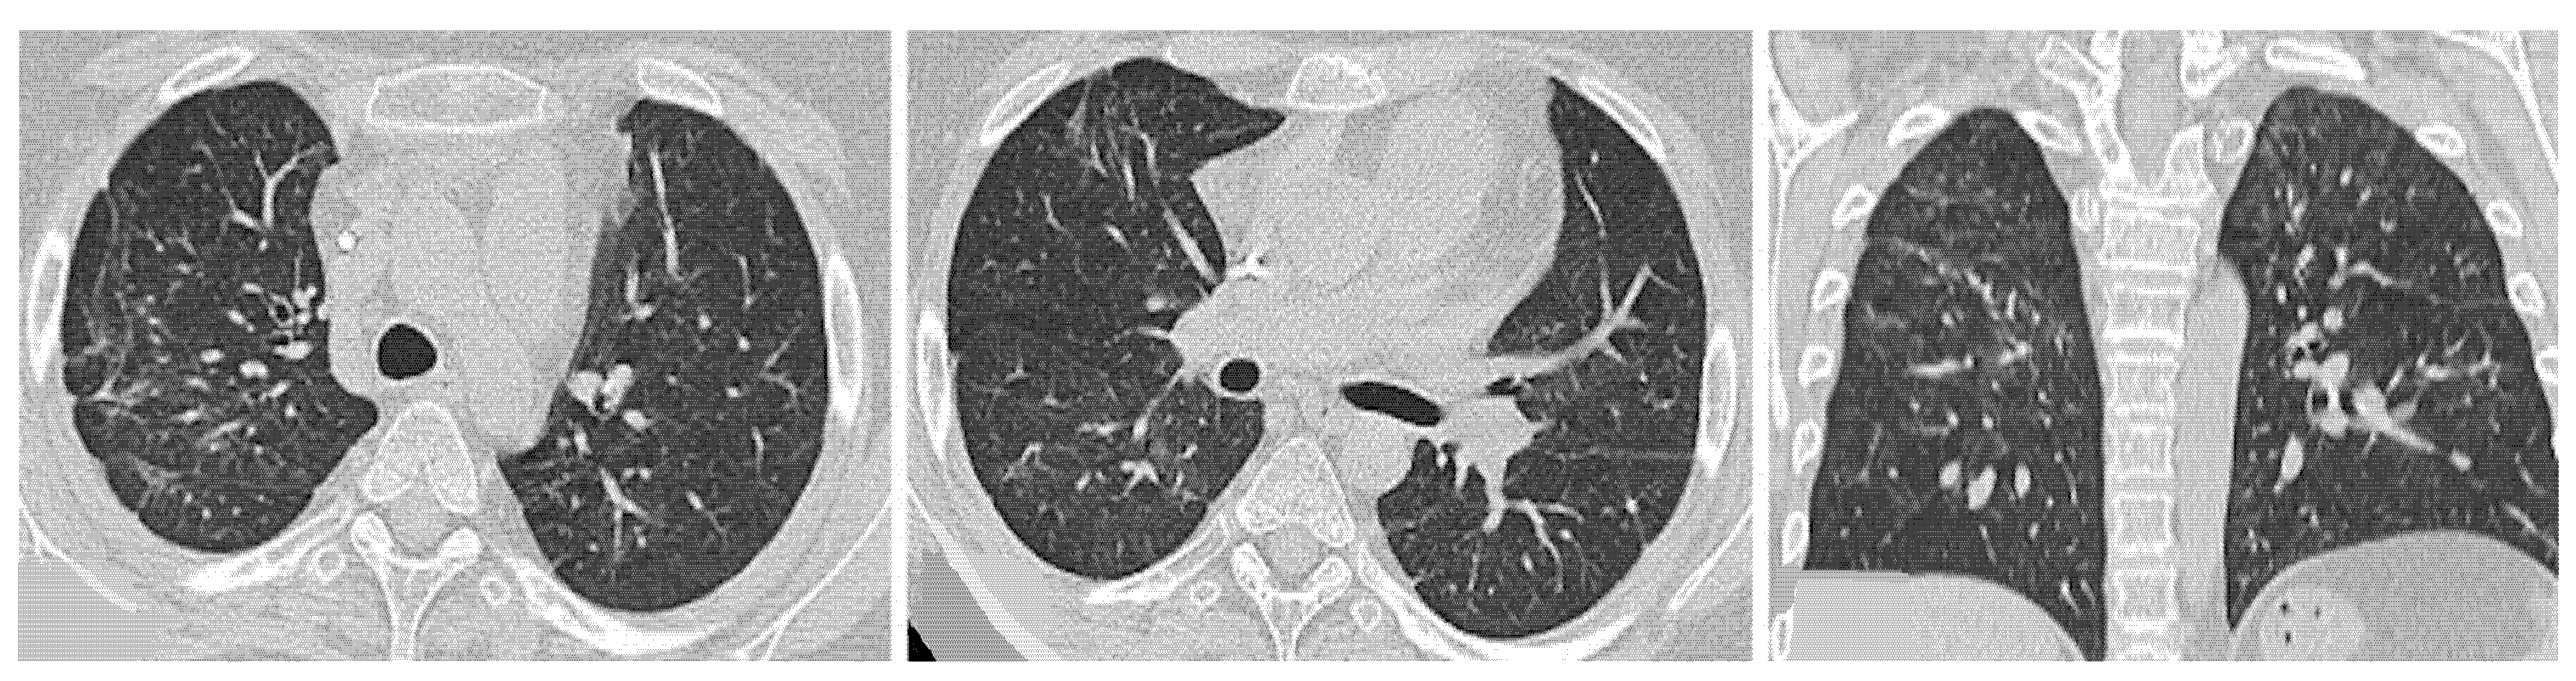

| Anti-ARS-Abs | Anti-MDA-5 Abs | ||

|---|---|---|---|

| Clinical course | subacute to chronic | acute rapidly progressive to subacute | |

| Lesions | GGO, reticulations, consolidations | consolidations, GGOs | |

| Distribution | Homogeneous; lower lung lobes, along bronchovascular bundles and lung periphery; loss of volume of lower lobes | Patchy; peripheral lower lobes or along the bronchovascular bundles | |

| CT pattern | NSIP OP NSIP-OP UIP DAD-unclassifiable | 50% 20% 25% 10% +/− | 20% 50% 25% <5% ++ |

| Prognosis | good response to treatment; possibility of relapses | Poorer prognosis |